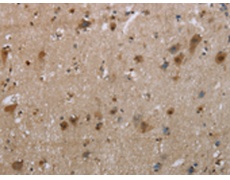

ELISA, IHC |

IHC positive control: |

Human brain and human thyroid cancer |